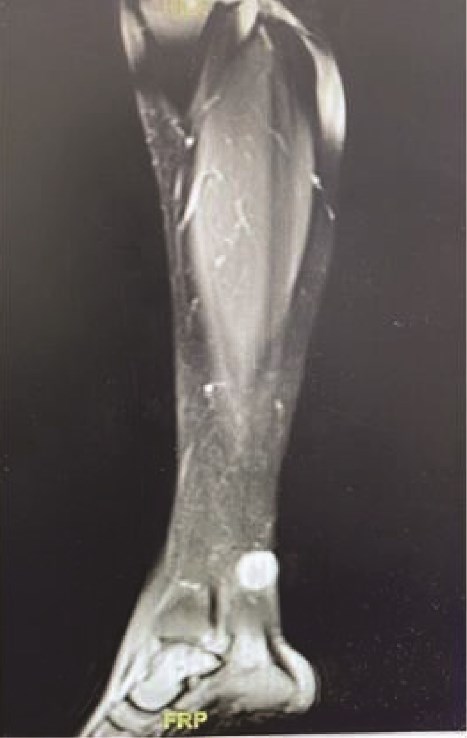

Upon general examination, the patient was conscious and vitally stable. Local examination of the ulcer revealed an irregular shape with black margins and brownish skin discolouration on the lower aspect of the left leg over the Achilles tendon. On palpation, tenderness, spontaneous bleeding, and pus discharge were noted. Laboratory investigations were unremarkable. A complementary magnetic resonance imaging (MRI) was performed and demonstrated a subcutaneous soft tissue mass on the posterior aspect of the lower leg, adjacent to the Achilles tendon, measuring 1.9 × 2.1 × 2 cm in dimensions as shown in Fig. 1a.

MRI demonstrating subcutaneous soft tissue mass on the posterior aspect of the lower left leg.